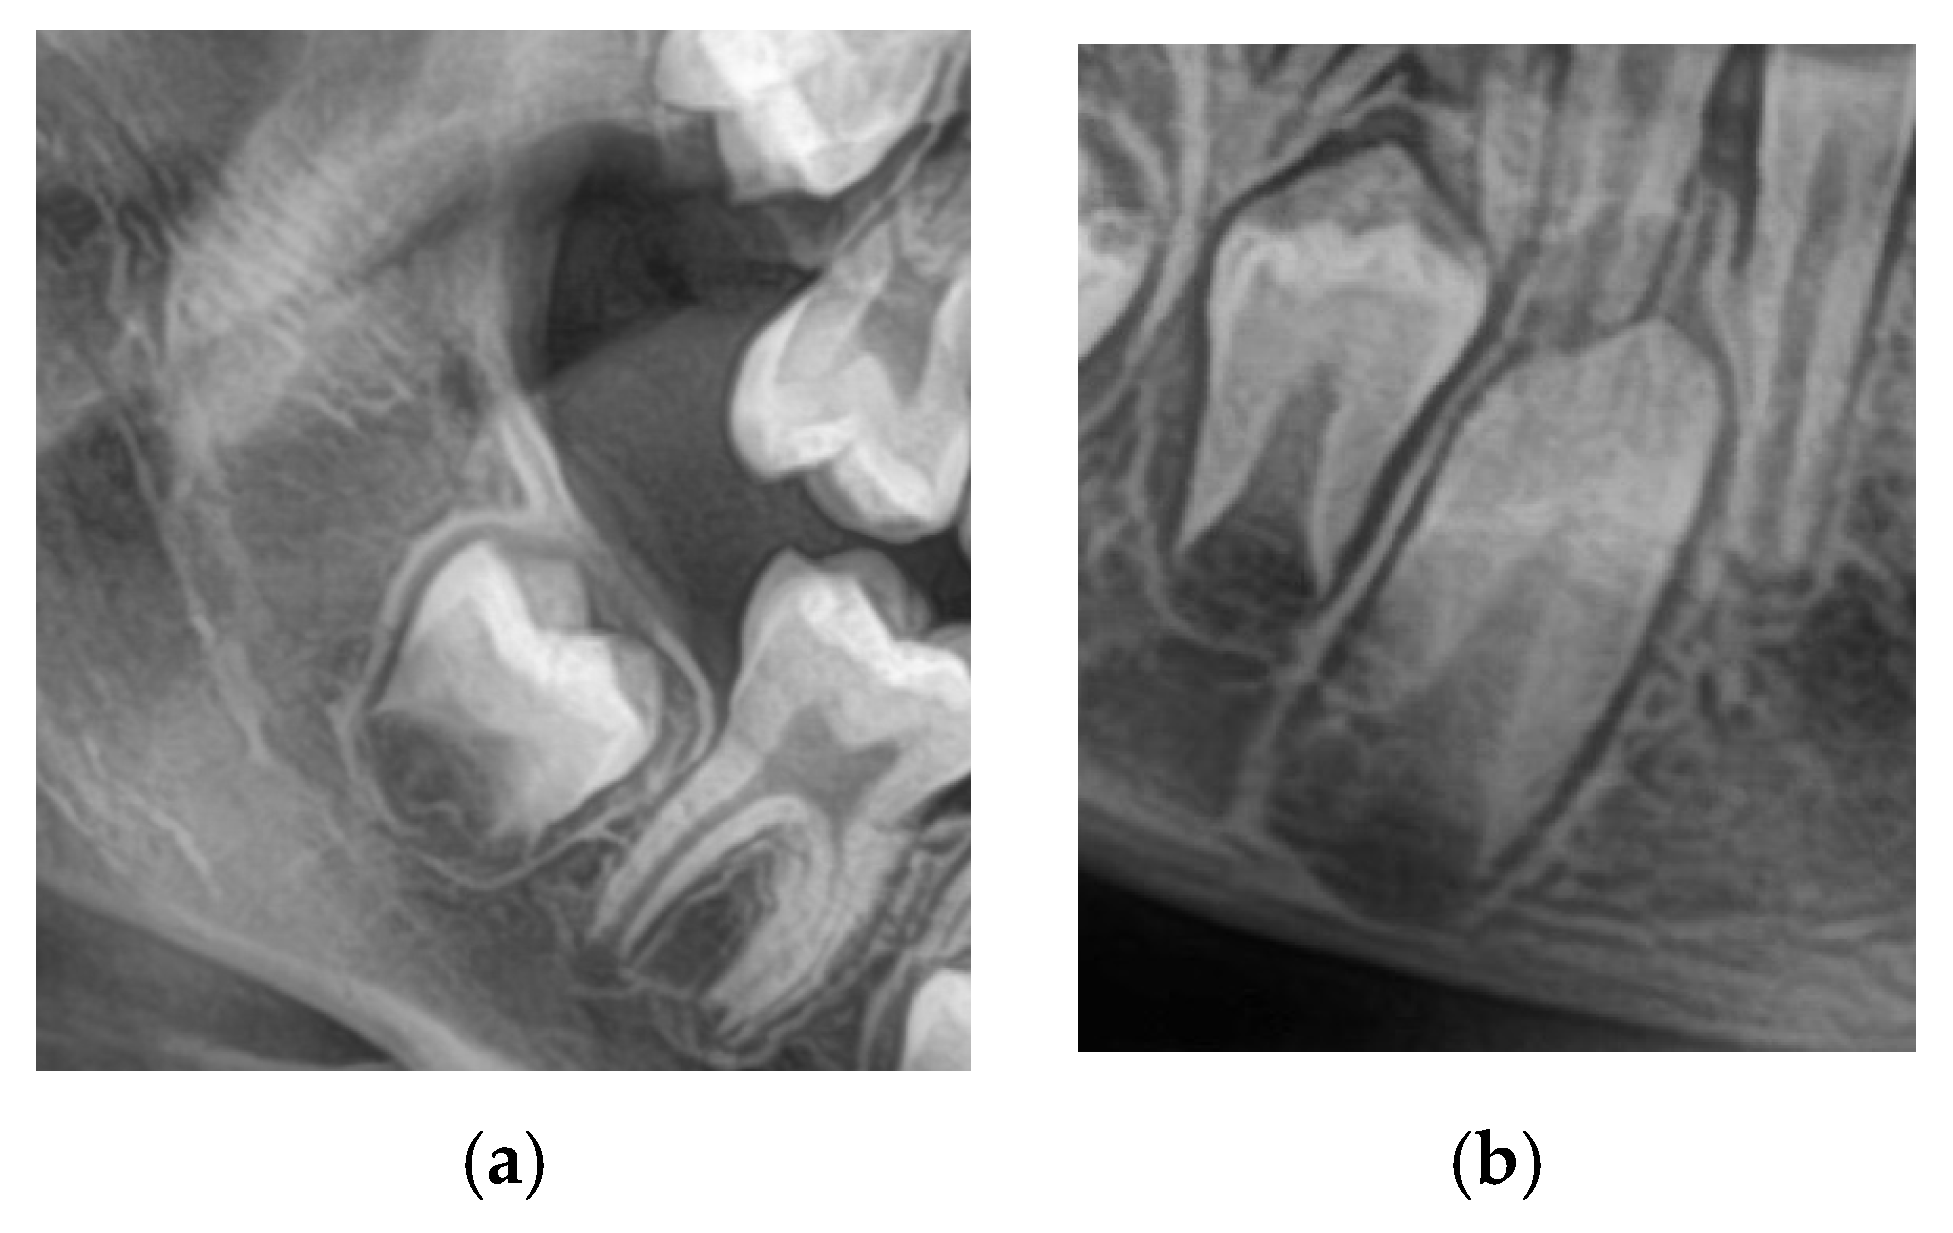

A total of 1200 digital OPGs were collected retrospectively from academic and private dental centers. The sample was 600 males and 600 females aged 8–16. The inclusion criteria were OPGs with adequate quality; both the lower 2nd molars and canines are clearly visualized as in

Figure 1, no systemic disease, craniofacial syndrome, and no previous orthodontic treatment. Examinations with inadequate image quality, overlapping dental structures, or incomplete records were excluded.

To standardize the assessment and preprocess the images for ML (Machine Learning), each image is individually cropped to isolate the region of interest (ROI) circumscribing the lower second molar and lower canine. Each of these cropped ROIs was saved as a separate image file and named according to the appropriate Demirjian stage. Such a narrowed-down query reduced noise in the form of background data, thereby providing more precise training input to CNN models.

Figure 2 shows the cropped images.

2.4. Image Preprocessing

The preprocessing technique is implemented on each image after annotation to standardize the data and enhance the model’s robustness. An image of the ROI surrounding the lower second molar and lower canine was manually cropped and resized to 128 × 128 pixels. Most background noise was removed by applying a non-local means filter, preserving anatomical boundaries from blurring. The pixel values were normalized to the range of (0, 1) values.